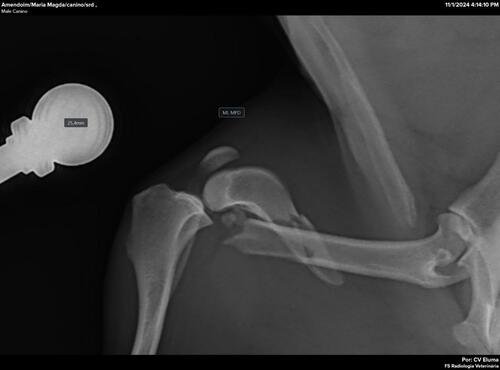

Ajude na cirurgia do fêmur do Amendoim

O Amendoim foi atropelado e abandonado nas ruas com um fêmur quebrado, mas foi resgatado e está internado, aguardando a cirurgia que ficou no valor de R$2.740,00 que precisa ser paga para que ele possa ser operado.Pedimos ajuda com qualquer ver tudo

O Amendoim foi atropelado e abandonado nas ruas com um fêmur quebrado, mas foi resgatado e está internado, aguardando a cirurgia que ficou no valor de R$2.740,00 que precisa ser paga para que ele possa ser operado.

Pedimos ajuda com qualquer valor!